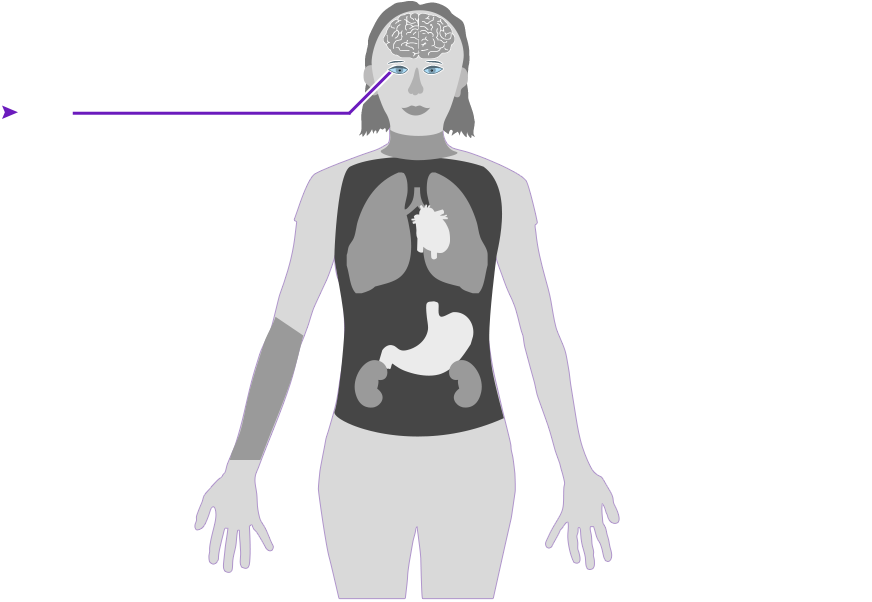

Check out how mercury can affect the human body. Click on the different parts of the body to see what can happen when people are poisoned by mercury. How serious these health effects are may vary depending on how much mercury gets into your body — and how long you breathe it in.

Health effect caused by breathing in high levels of mercury vapors (fumes) over a short period of time

Health effect caused by breathing in high levels of mercury vapors (fumes) over a short period of time  Health effect caused by breathing in lower levels of mercury vapors over a long period of time